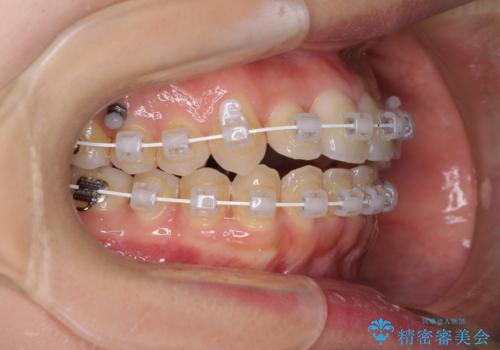

- 矯正装置

- 審美装置

- 前歯のデコボコを気にして来院された患者様です。

上顎右側犬歯が八重歯になっており、それによって奥歯が前方に移動しているため、右側の咬み合わせの改善が必要と判断されました。

マウスピース矯正では改善に時間がかかる、あるいは改善しきれない可能性があることを伝えたところ、短期間で確実に治療ができるワイヤー矯正を選択されました。

より治療を速やかに行うため、上顎右側にアンカースクリューを使用し、目標としていた1年半ほどで治療を終えることができました。